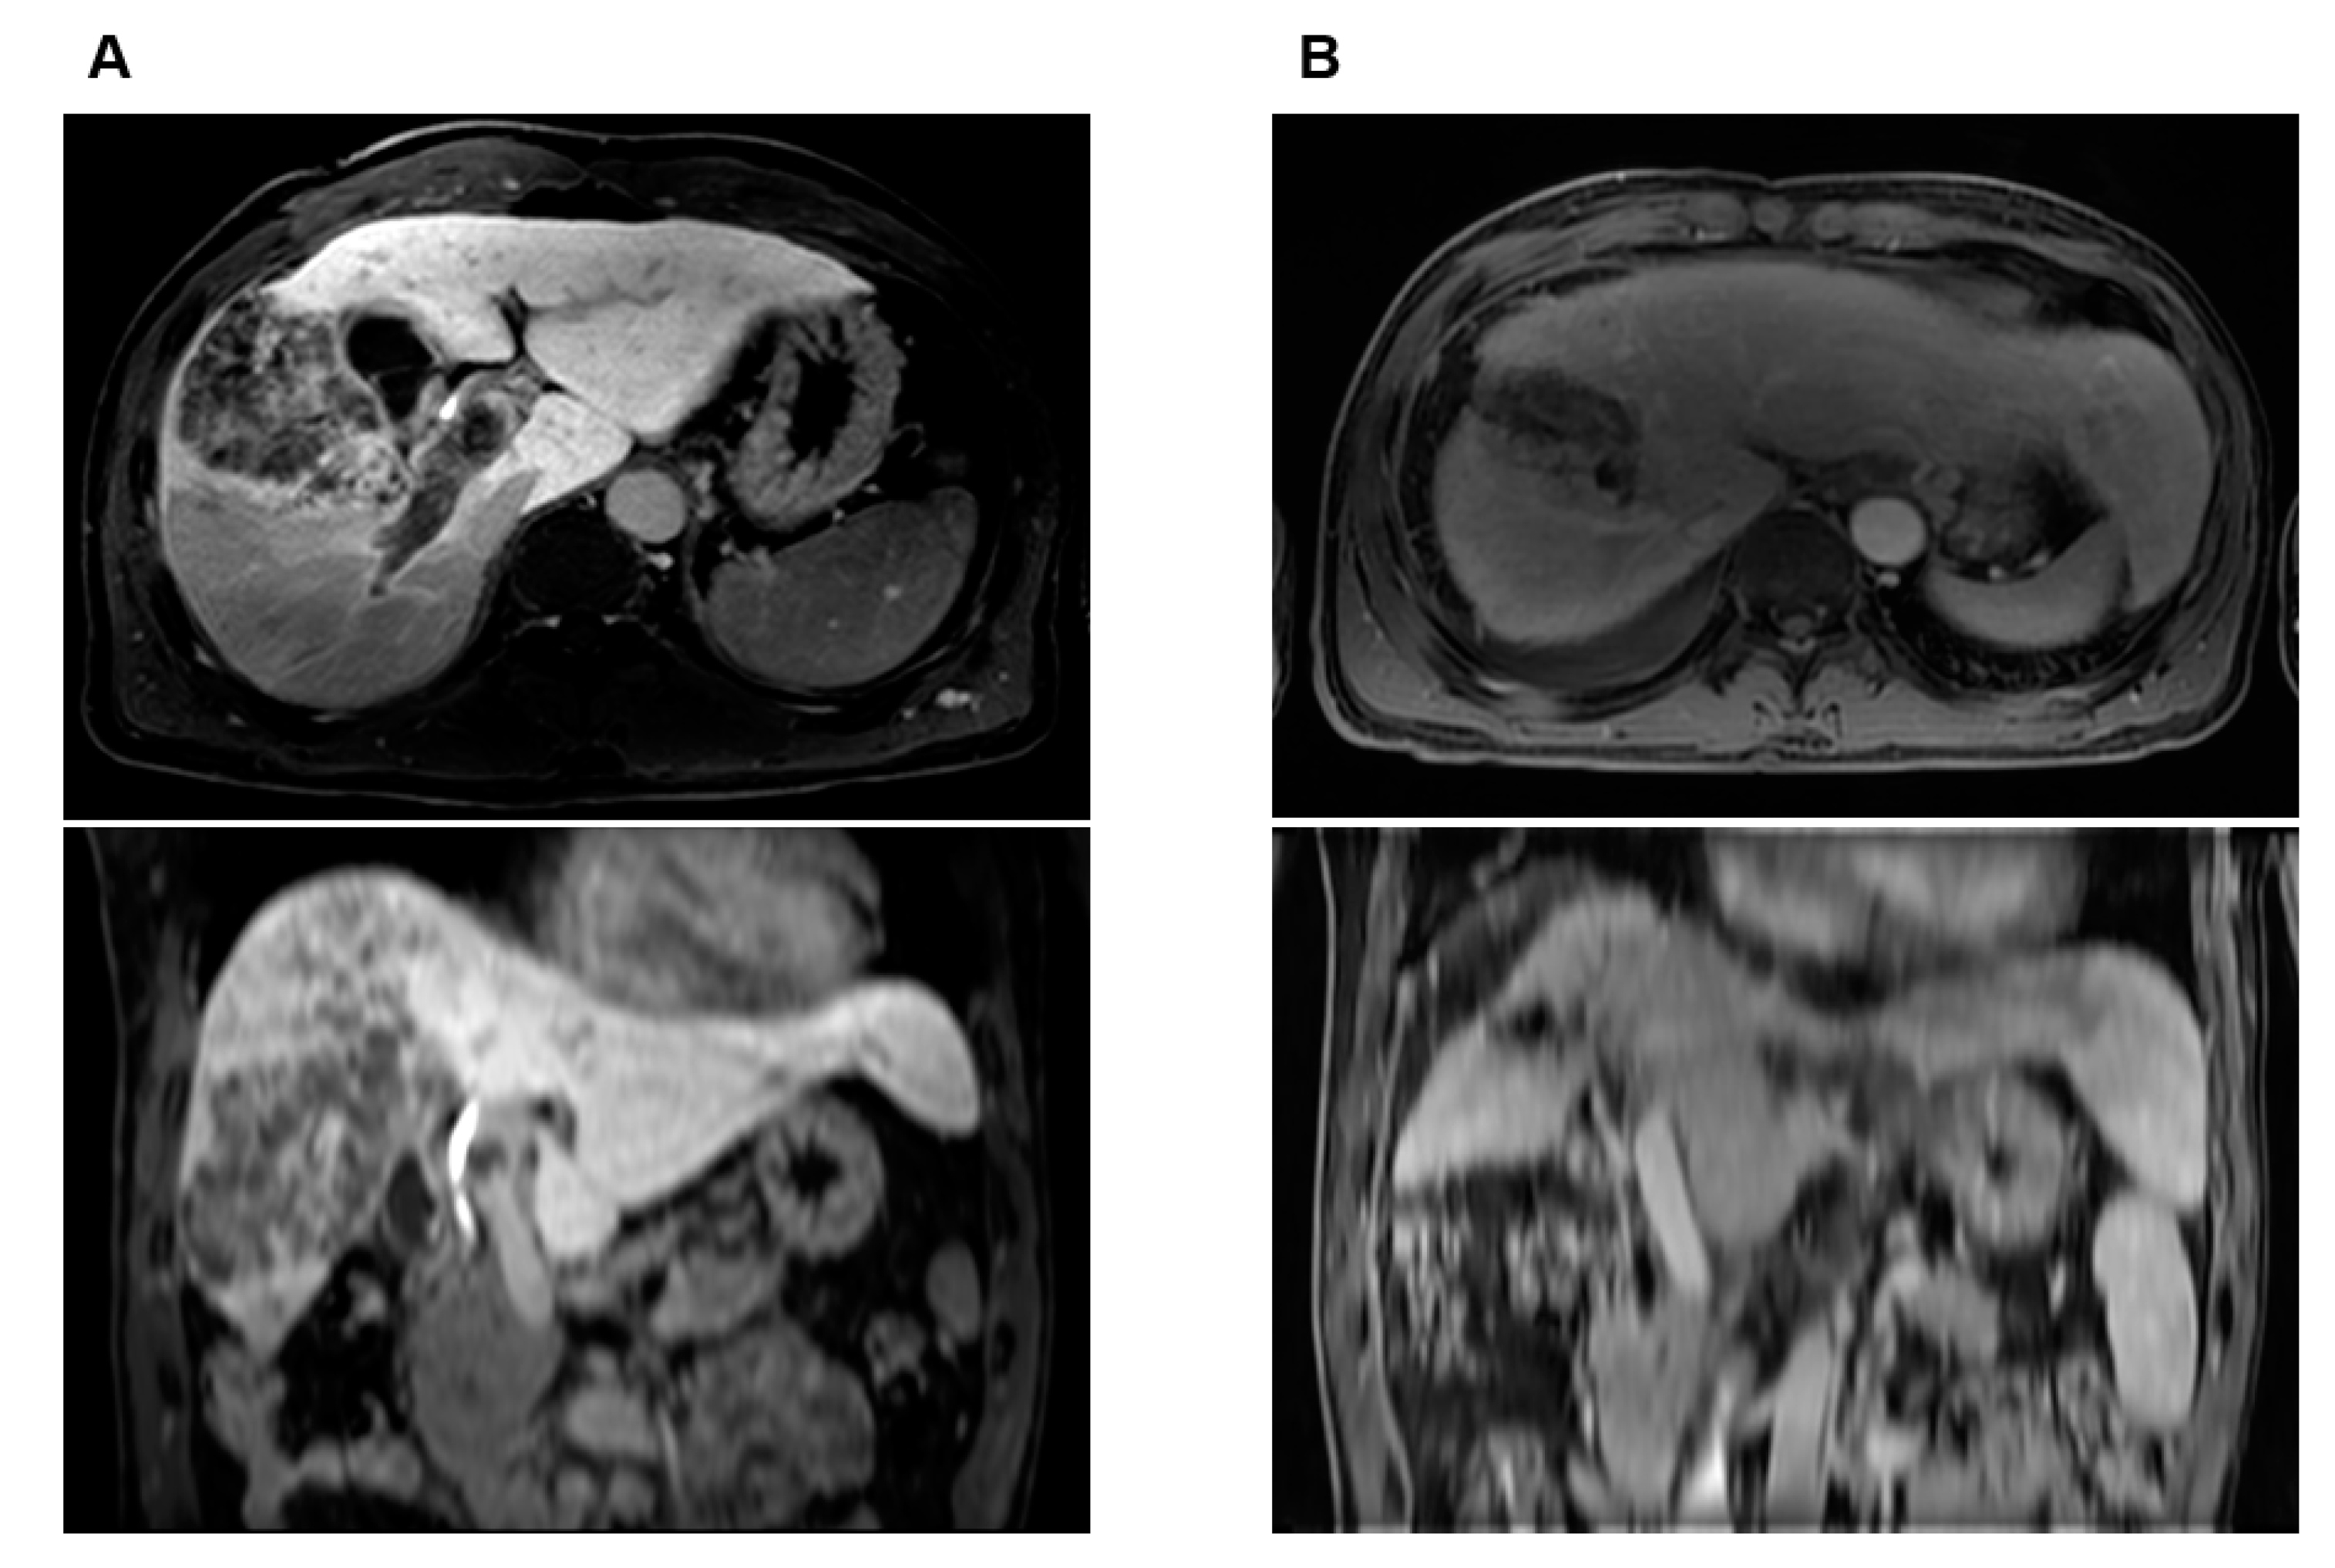

Figure 5.

Case illustration of a 51-year-old male patient who received liver-directed concurrent chemoradiotherapy (LD-CCRT) followed by right lobectomy of the liver. Initial status was a 10.5 cm tumor involving both hepatic lobes associated with extensive tumor thrombosis involving right and main portal veins as well as elevated tumor markers. After LD-CCRT, significant tumor response was obtained with decreased tumor markers. Right lobectomy of liver was performed 4.5 months after the conclusion of LD-CCRT, and pathology report showed total necrotic tumor with no evidence of tumor thrombosis at portal vein. (A) Pretreatment axial and coronal MRI images showing locally advanced HCC with PVTT in right and main portal veins, (B) axial and coronal MRI images showing successful downstaging of tumor with reduced extent of PVTT 3 months after LD-CCRT. A dramatic decrease in tumor markers was also noted: alpha-fetoprotein and protein induced by vitamin K absence-II values of 63,430.93 ng/mL and 131 mAU/mL initially dropped to 4.97 ng/mL and 16 mAU/mL one month after LD-CCRT, respectively. The patient is alive without evidence of tumor recurrence at 101.5 months.